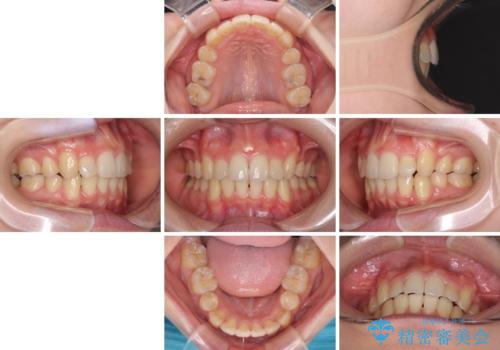

気になる八重歯を治したい ワイヤー装置での抜歯矯正

- 上下の八重歯や乱杭歯を気にして来院され患者様です。

スペースを確保するため、上下左右の第一小臼歯を抜歯し、ワイヤー装置に矯正することとしました。

結婚式の予定があったため、まずは前歯をきれいに整えるようにしました。

結婚式の時には一時的に前歯の装置を外し、口元を気にせず笑える結婚式を迎えることができました。

その後スペースを閉じるために時間を要しましたが、満足のいく仕上がりとなりました。